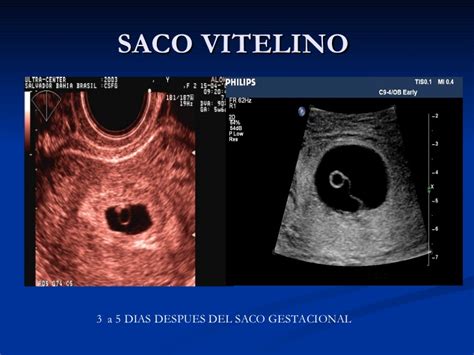

El embrión puede visualizarse por primera vez en el útero con un transductor lineal de 5-10 MHz entre los días 9-10, presentando un saco vitelino anecoico (no ecogénico) de 4 mm de diámetro. El embrión esférico se desplaza por la luz de los cuernos uterinos y el cuerpo del útero entre los días 6 y 16. Inicialmente, se observa una línea blanca brillante (ecogénica) en el aspecto dorsal y, a veces, ventral, conocida como reflector especular. Este artefacto se produce cuando el haz de ultrasonido incide perpendicularmente sobre la superficie lisa y ancha del embrión.

Al día 17-18, el embrión adquiere una forma característica de "púa de guitarra". Al día 21, el embrión propiamente dicho es visible en la cara ventral del saco vitelino. A los 24 días, la cavidad alantoidea se presenta como un compartimento anecoico ventral al embrión.

Es a los 25 días cuando debe detectarse el latido cardíaco en el embrión. A medida que la cavidad alantoidea aumenta de tamaño, el saco vitelino comprime una porción menor del embrión. La posición del alantoides, el tamaño relativo de la cavidad alantoidea y la regresión del saco vitelino pueden indicar el estadio de la gestación entre los días 24 y 45.

A los 30 días, la cavidad alantoidea ocupa aproximadamente la mitad del embrión, de forma que el tamaño del saco vitelino es equivalente al de la cavidad alantoidea. A los 45 días, la única cavidad líquida visible es la alantoidea, y el feto parece estar suspendido de la pared dorsal del útero por su cordón umbilical, en posición de decúbito dorsal.